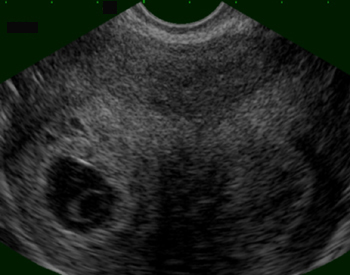

Utérus cloisonné. Grossesse débutante dans l’une des cornes (Cliché : Dr. C. TALMANT)